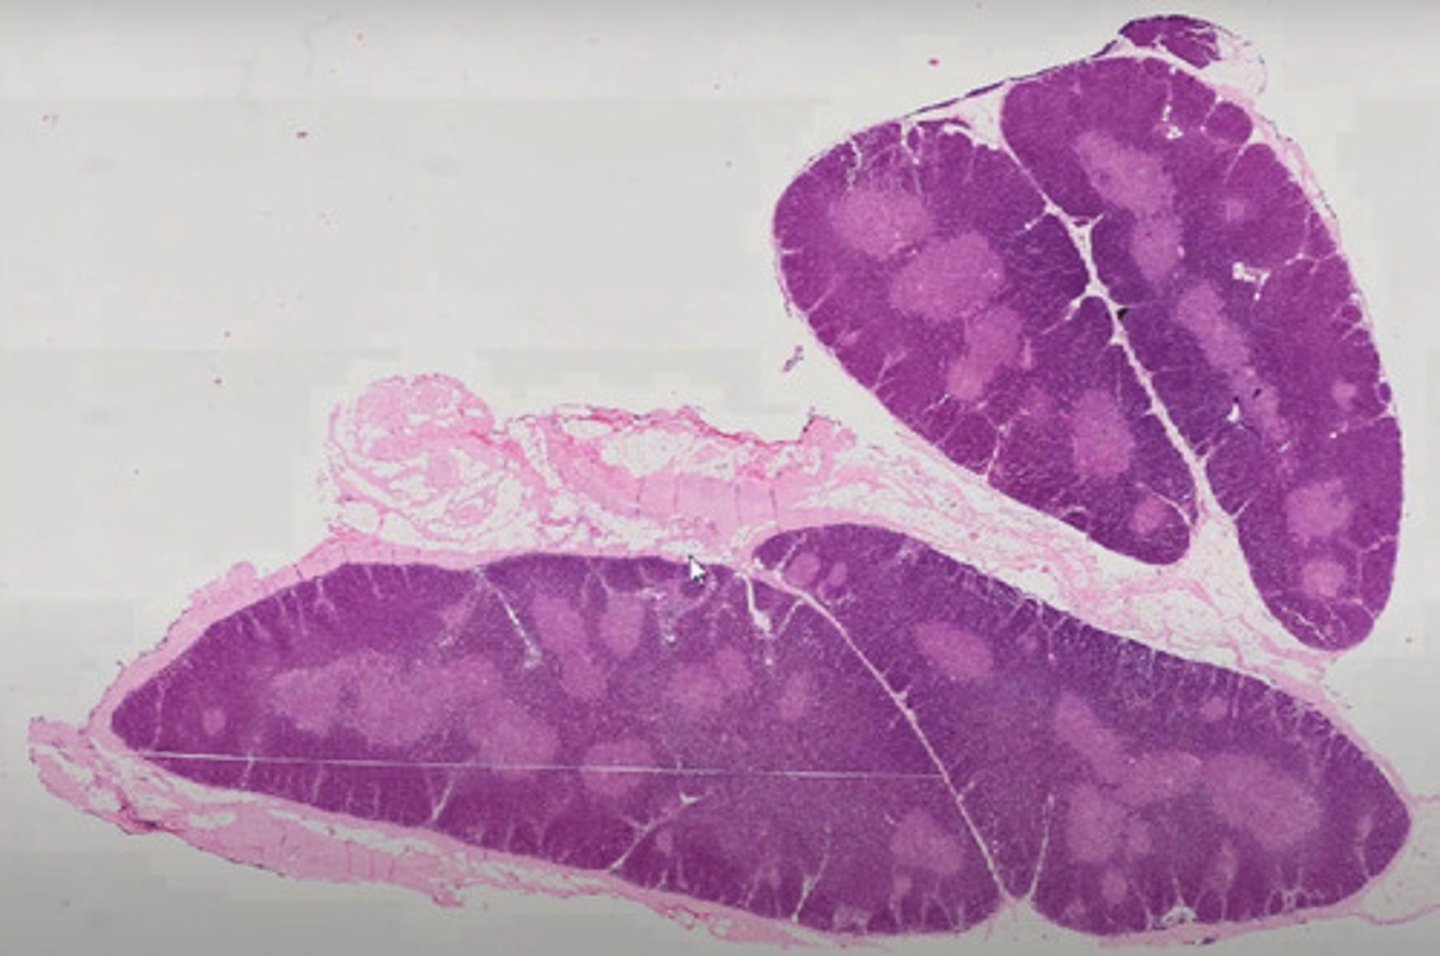

Wyrostek robaczkowy (H+E)